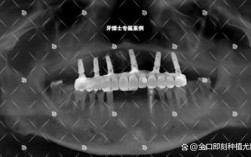

A:不一定,术后3天内疼痛加剧且止痛药无效,可能是局部血肿(伤口内出血形成血块压迫神经)或感染(如牙龈炎、骨炎),建议及时联系医生,通过检查(如拍X光片)判断原因:血肿可能需切开引流,感染则需加强抗炎治疗(如调整抗生素),若术后1周后仍出现持续性剧痛,或伴随种植体松动、流脓,可能提示种植体骨结合不良,需进一步评估是否需要处理种植体,但这种情况较为少见。